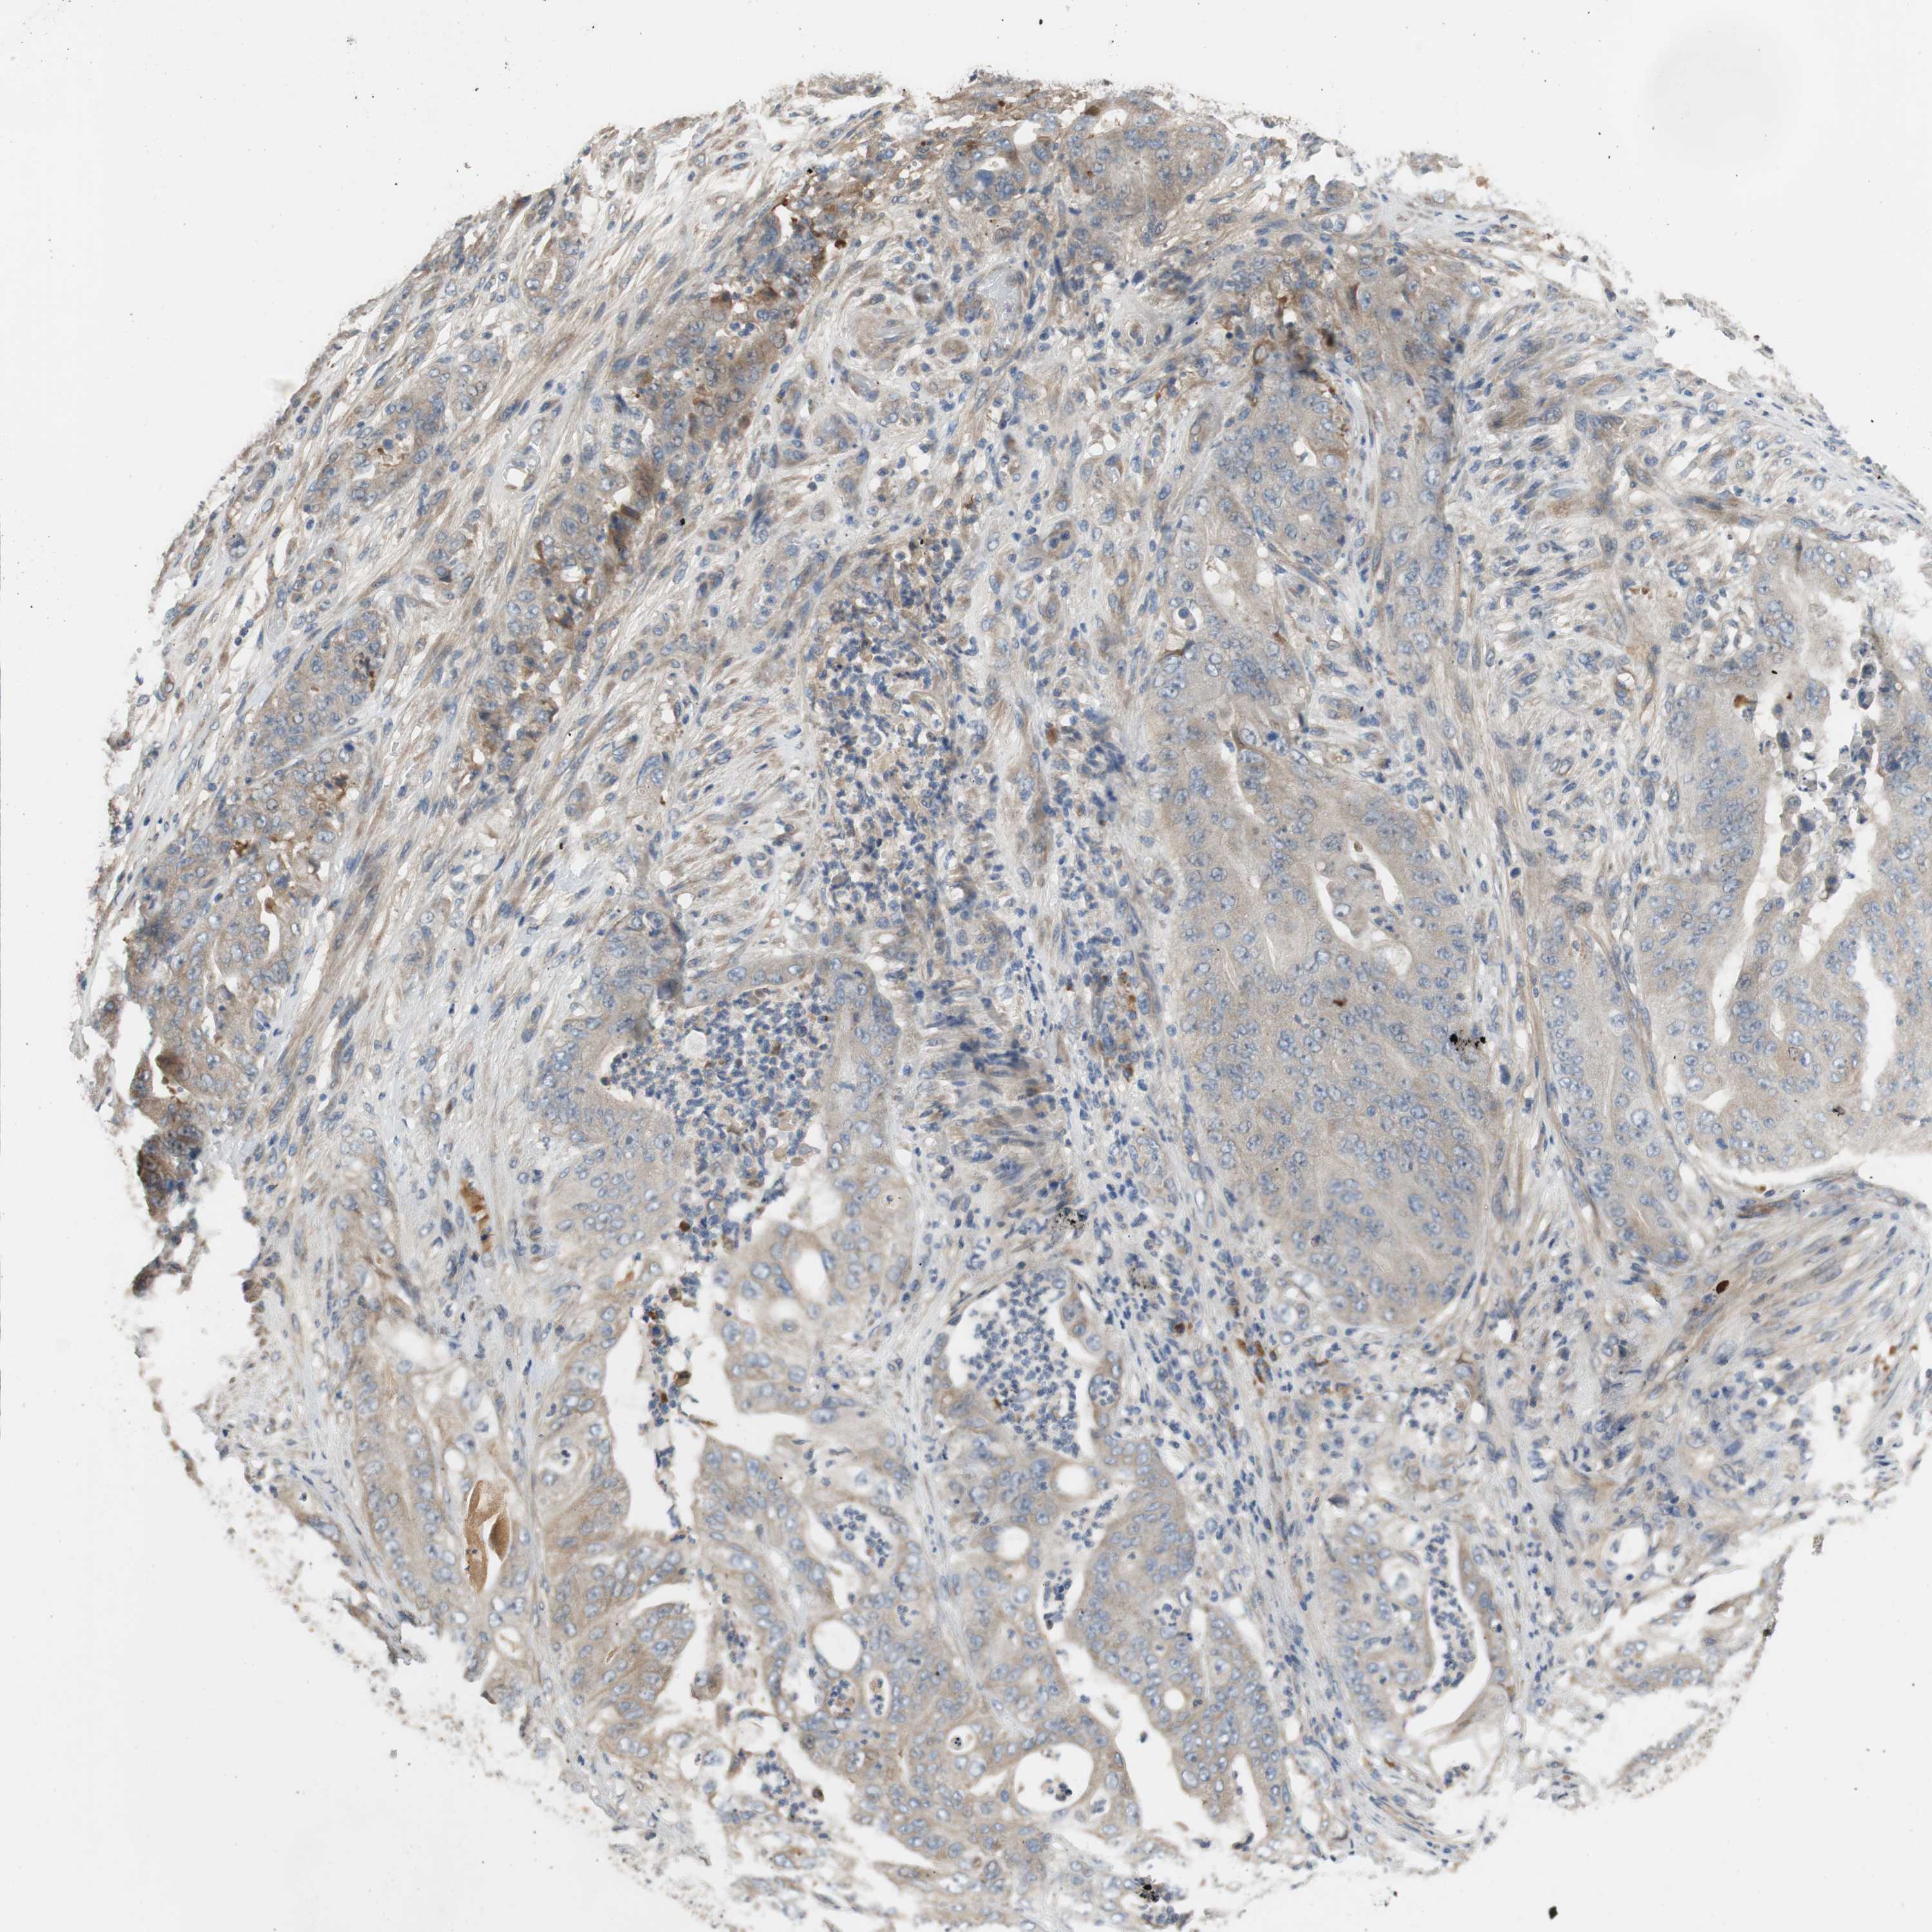

STOMACH CANCER - Protein expressioni

A mouse-over function shows sample information and annotation data. Click on an image to view it in a full screen mode. Samples can be filtered based on level of antibody staining by selecting one or several of the following categories: high, medium, low and not detected. The assay and annotation is described here.

Note that samples used for immunohistochemistry by the Human Protein Atlas do not correspond to samples in the TCGA dataset.

Antibody stainingi

Antibody staining in the annotated cell types in the current human tissue is reported as not detected, low, medium, or high, based on conventional immunohistochemistry profiling in selected tissues. This score is based on the combination of the staining intensity and fraction of stained cells.

Each image is clickable and will lead to virtual microscopy that enables deeper exploration of all samples and also displays staining intensity scores, fraction scores and subcellular localization as well as patient and tissue information for each sample.

HPA046356

Staining

Low

Weak

<25%

Cytoplasmic/membranous

Adenocarcinoma, NOS